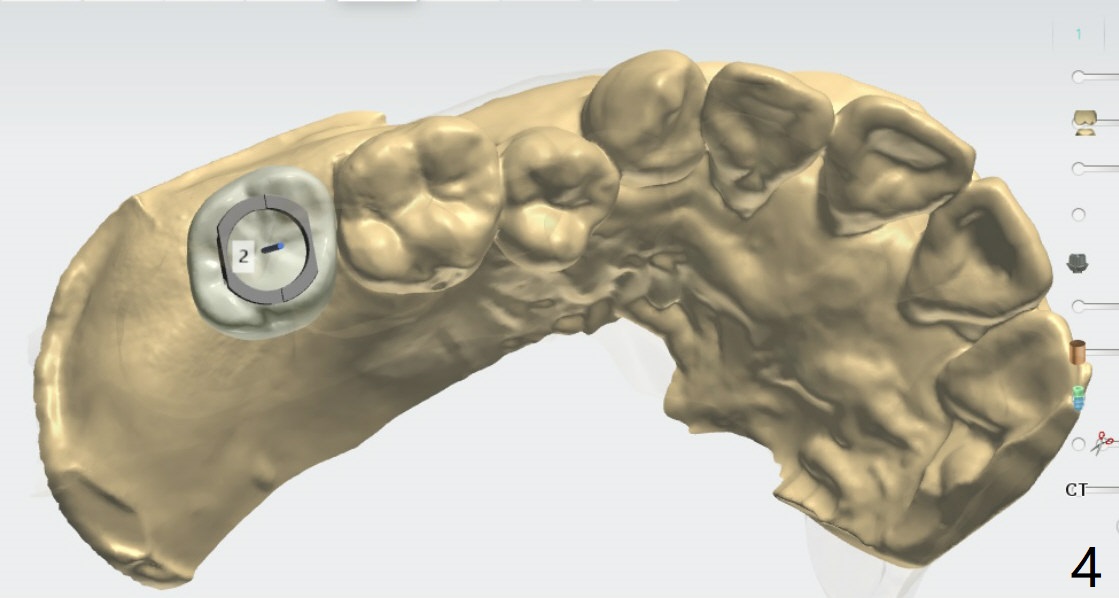

PRF,粘性骨粉用于上颌窦提升

Nearly 5 months post socket preservation. Prepare 4 mm Biopsy Punch. After light use of Tissue Punch to make mark in the gingiva, remove the guide, use the 4 mm Biopsy Punch to harvest the tissue and place the latter in PRF dappen dish. If implant torque is low, place bone graft over the implant, return the tissue to the site and use perio glue for fixation. Finally apply acrylic dressing. Prepare Sinus Approach Kit and 4x10 mm IS dummy implant.